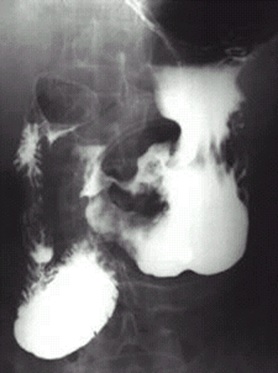

04卷-5.病史:男性,62歲,上腹不適,惡心、嘔吐5個月,大便潛血陽性3周。診斷(本題滿分2.00分)

A.十二指腸球潰瘍

B.胃潰瘍

C.胃癌

D.胃炎

本題答案:C

題目解析:【該題針對“X線-消化道穿孔”知識點進(jìn)行考核】